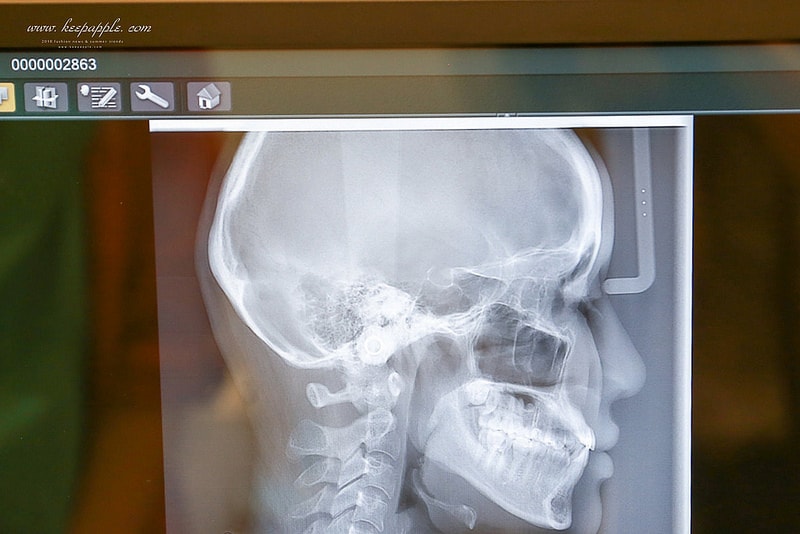

「X光室」使用的是近幾個月出的 Veraview X800 斷層掃描儀

這可是全台第一、二家進的機器

在台灣只有兩家有 (另一台在台北)

精準度比一般的還高

我覺得這超厲害的!!!

這次是要來做隱適美的事前功課

諮詢之前會先到X光室拍攝

再和醫師討論之後需要的療程

運用最新尖端的設備

能更精準地了解客人想改善的地方

像我的部分就是不需要拔牙

只是需要讓位置慢慢變對

醫生說我大概只要戴一年多呢